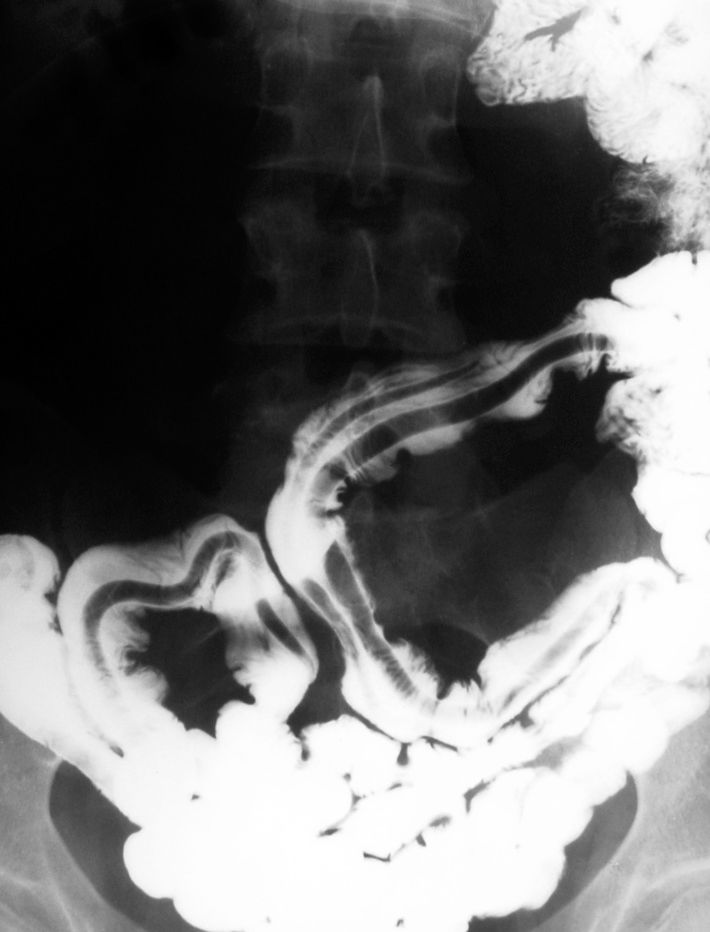

Low-dose CT screening for lung cancer does present risks of false-positives and over-diagnosis, but for heavy or ex-smokers, it is worth it.